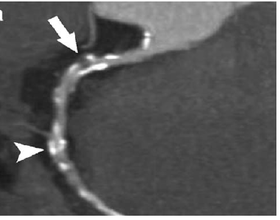

Computed tomography angiography

Computed tomography angiography (CTA), an imaging methodology using a ring-shaped machine with an X-Ray source spinning around the circular path so as to bathe the inner circle with a uniform and known X-Ray density. Cardiology uses are growing with the incredible developments in CT technology. Currently, multidetector CT, specially the 64 detector-CT are allowing to make cardiac studies in just a few seconds (less than 10 seconds, depending on the equipment and protocol used). These images are reconstructed using algorithms and software. Great development and growth will be seen in the short term, allowing radiologists to diagnose cardiac artery disease without anesthesia and in a non-invasive way.